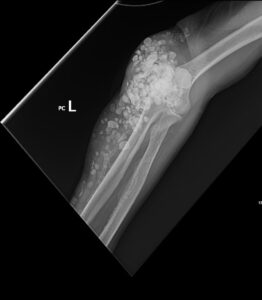

Calcinosis Cutis. Elbow XR, External Oblique. JETem 2025

Calcinosis Cutis. Elbow XR External Oblique. JETem 2025